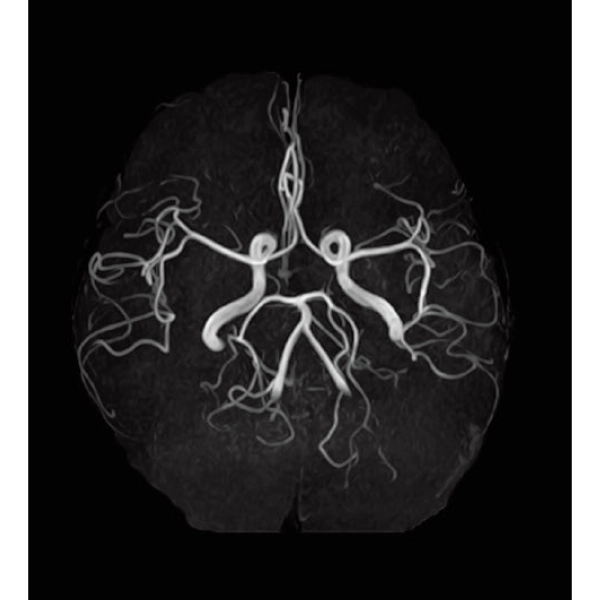

3DTOF MRA (MIP), 1:26